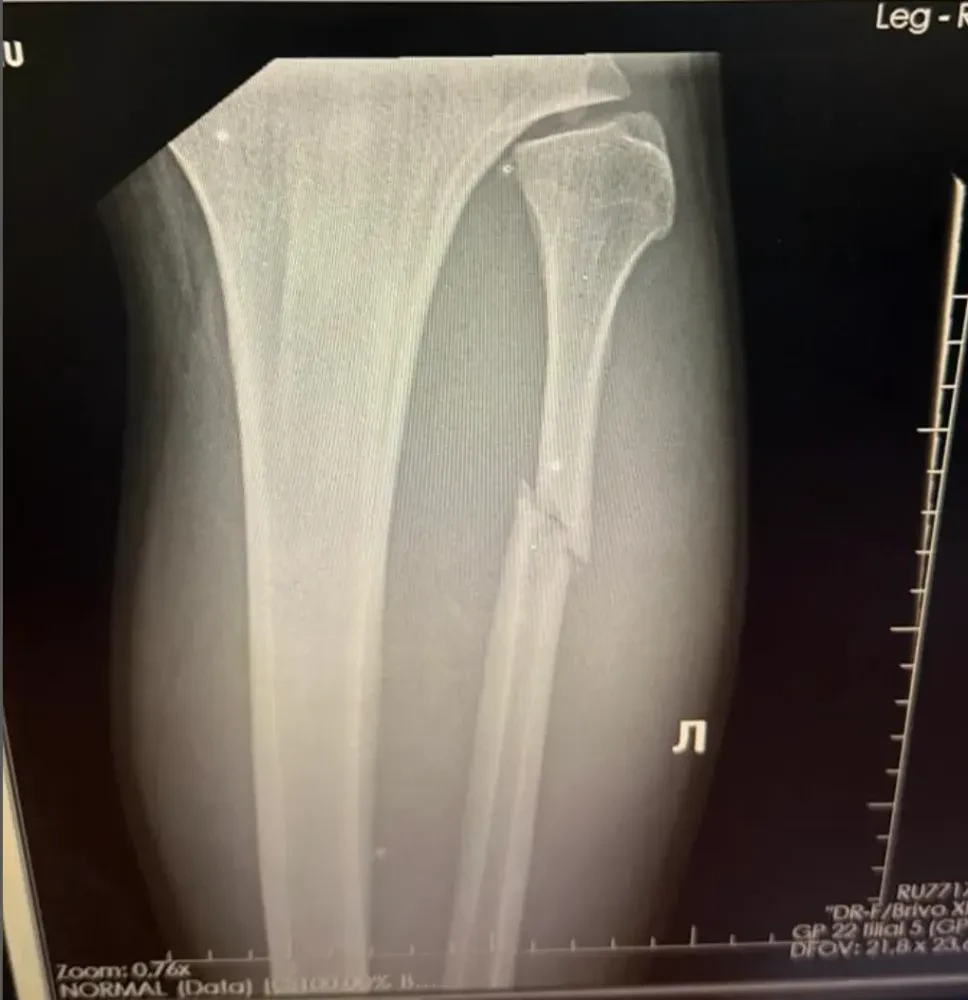

Chỉ đến khi Walker đến gặp bác sĩ và nhận kết quả chụp X-quang, sự thật mới được phơi bày. Hình ảnh cho thấy xương mác của anh đã gãy làm đôi. Chính anh cũng phải sững sờ.

“Lúc đầu, tôi cảm thấy rất đau nhưng cố tự nhủ, cứ lờ cơn đau đi rồi ba ngày sau sẽ ổn thôi,” anh nói. “Tôi ngủ một giấc, thức dậy và chân còn đau hơn. Tôi vẫn không tin. Tôi đến gặp bác sĩ và nói, ‘Tôi nghĩ chân tôi gãy thật rồi.’ Khi bác sĩ cho tôi xem phim chụp, tôi không thể tin vào mắt mình. Trời đất ơi, chân mình gãy thật sao? Tôi không muốn tin điều đó.”